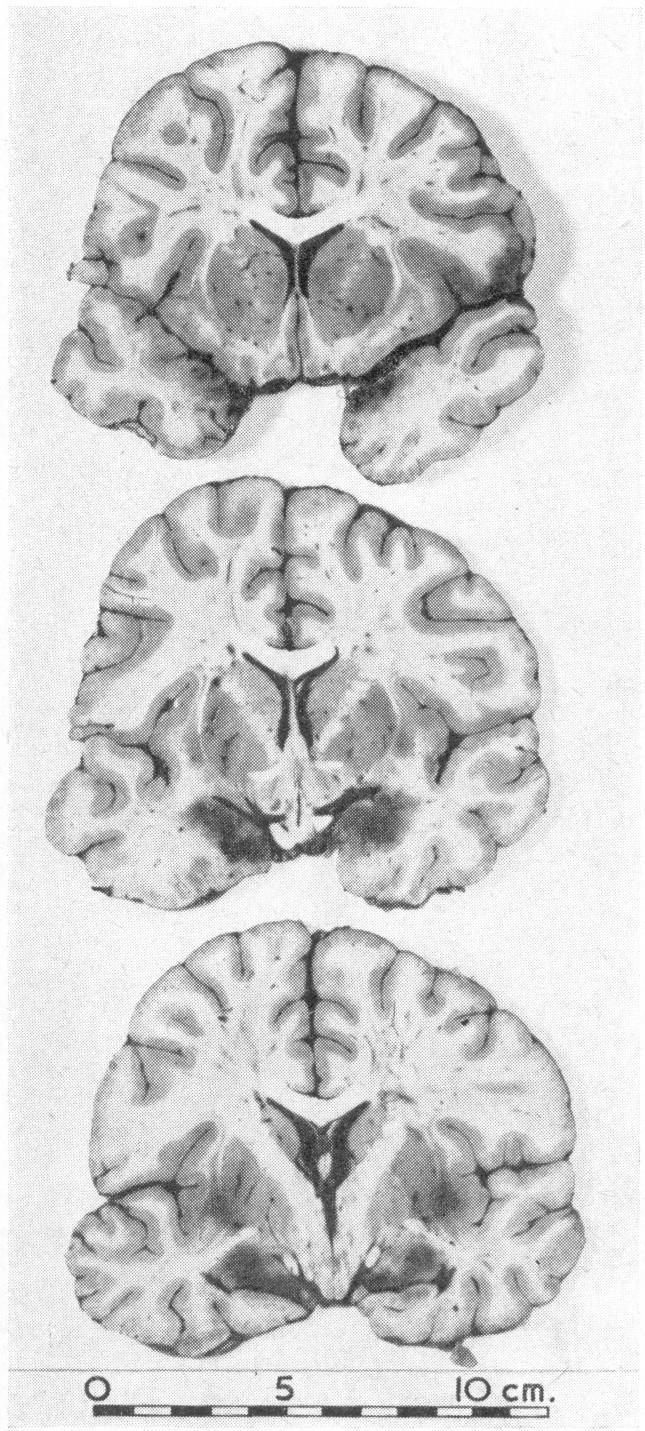

Association of brain damage with therapeutic abortion induced by amniotic-fluid replacement: report of two cases.

Br Med J. 1966 Apr 23;1(5494):1010-3. doi: 10.1136/bmj.1.5494.1010.